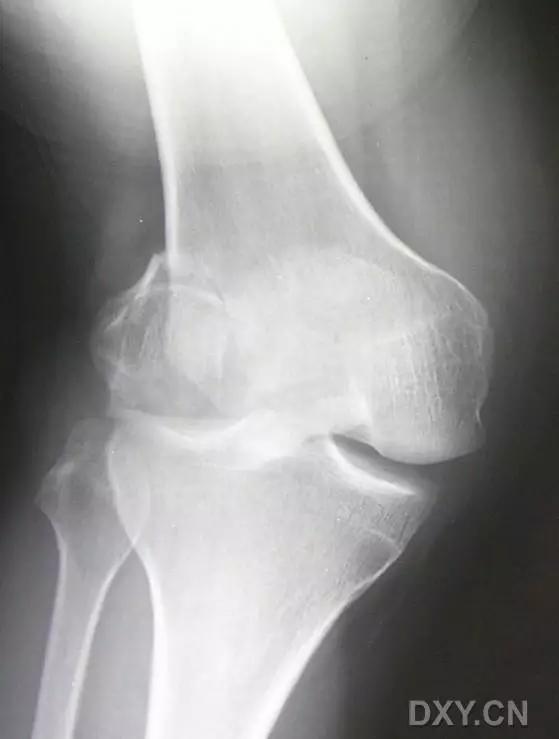

8. Segond 骨折和反向 Segond 骨折

(1)Segond 骨折

是发生在胫骨平台外侧的垂直撕脱性骨折。这种骨折在前后位 X 线片上显示最佳。屈曲位时膝关节受到内旋*力暴**作用,导致皮质骨撕脱性骨折,这种骨折常发生在运动员身上。

常引起股骨内髁和胫骨平台后内侧骨挫伤,75%~100% 的患者伴前交叉韧带断裂,33% 的患者伴外侧半月板损伤。

一位足球运动员的 Segond 骨折。A 正位片示关节线下方胫骨外侧皮质撕脱(箭头)。B MRI 冠状位 T1 加权像示附着于髂胫带的骨折碎片(空箭头)(来源:Radiol Clin N Am 53 (2015) 737–755,YU,Ohio)